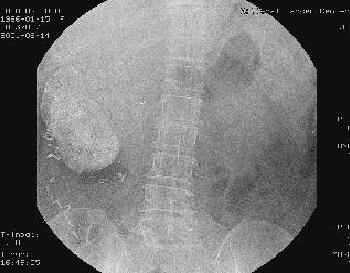

○ 배설성요로조영술

신실질에 발생한 신종물을 평가하기에는 불충분하며, 신윤곽의 변화, 신배의 이상, 신실질내의 석회화음영 등의 소견이 있는 경우에는 신종물을 의심하게 됩니다.

그림 2. 다발성 폐전이가 있는 단순 흉부 촬영사진